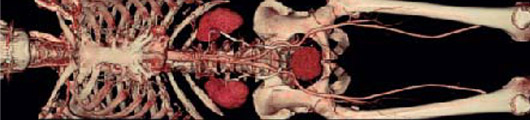

Our new SOMATOM Sensation CT scanner allows the routine use of high performance Multi-slice CT, providing extended coverage of anatomical areas while producing images with higher detail:

• Vasculature evaluation of the head, neck, thorax, abdomen, pelvis and extremities using CT Angiography.

• Evaluation of osteopathic and traumatic alterations of bone surface using 3-dimensional imaging.

• Computed tomography angiograms (CTA) excel at detecting significant narrowing of a blood vessel or artery that could require catheter-based intervention or surgery (such as bypassing).